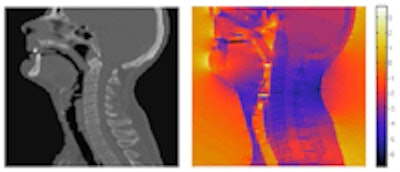

![]() |

| CT of the head-and-neck area (left) and the magnetic field distribution in ppm of the nominal value (right). |

The researchers note that the image correction scheme could prove particularly valuable for imaging small radiotherapy targets within heterogeneous anatomies. In head-and-neck cases, for example, where tissue/air/bone transitions cause large field inhomogeneity, MR images recorded with a gradient strength of 1 mTm-1 can be distorted by as much as 9 mm.